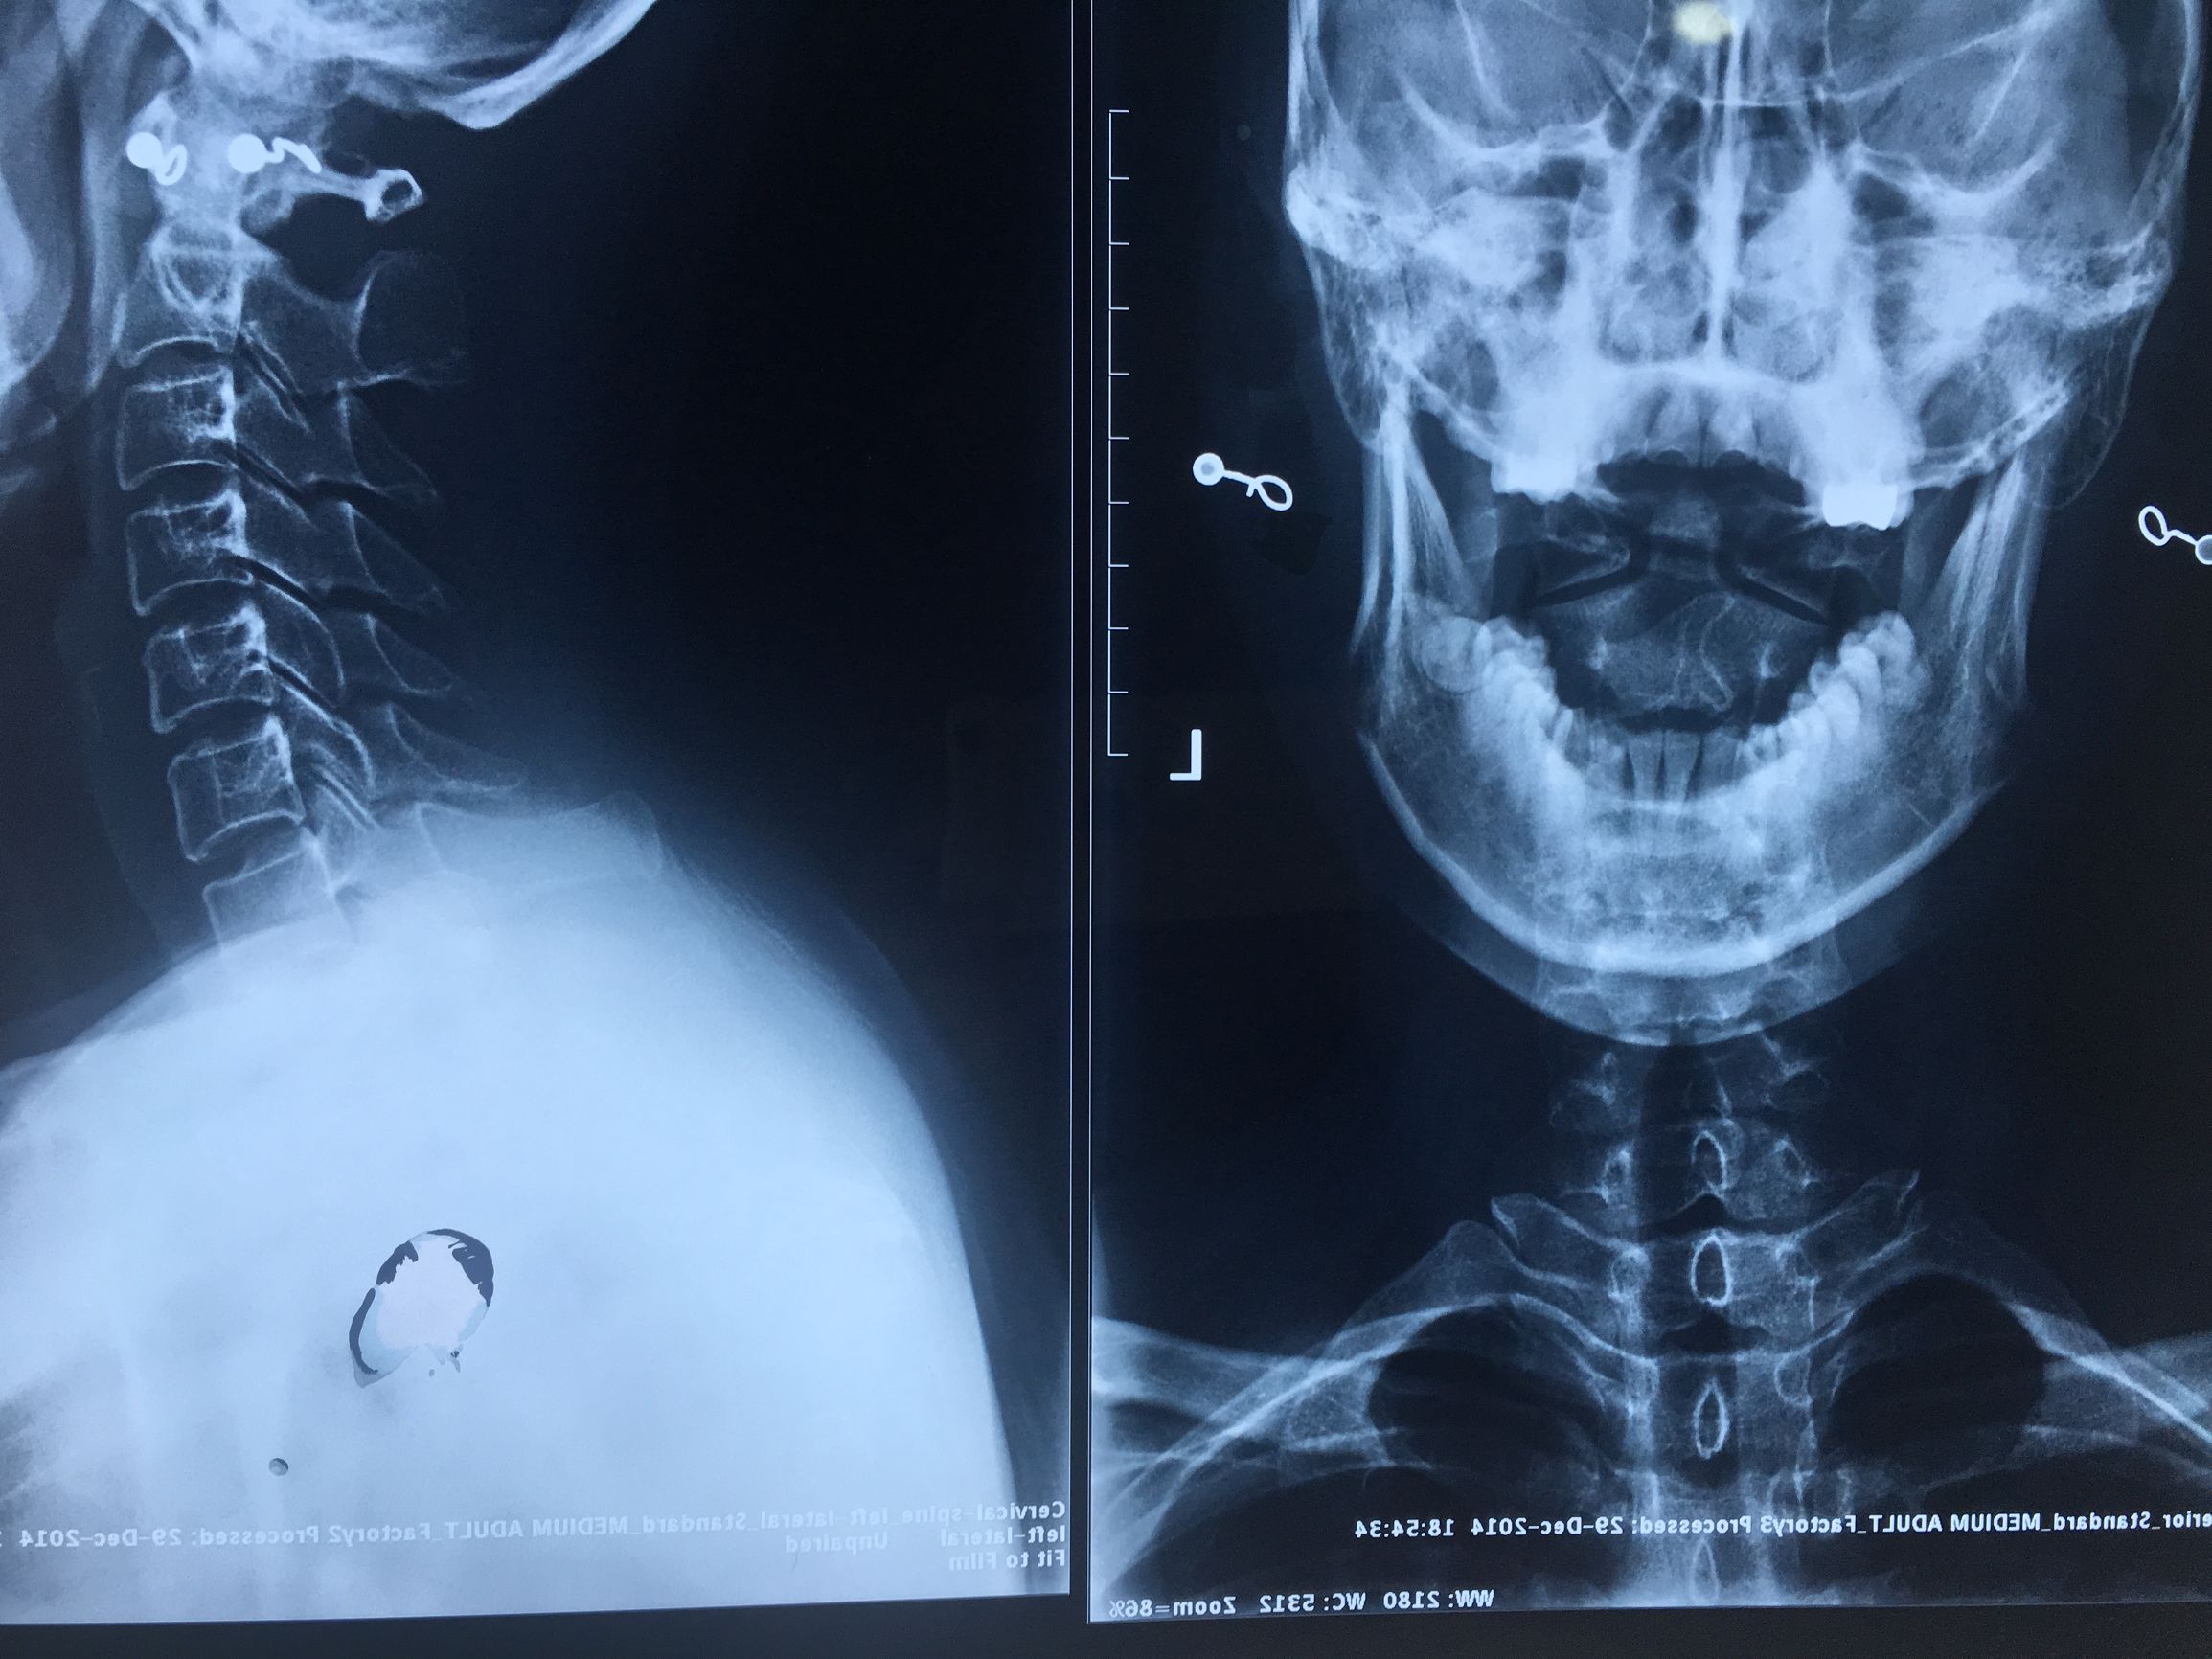

脊椎不仅是人的中轴线,更是人的中枢部位,如果连专业的诊断都没有,治了疼,疼了治,不如不治呢!如图孙彦昆医师正在给病人做脊椎矫正。